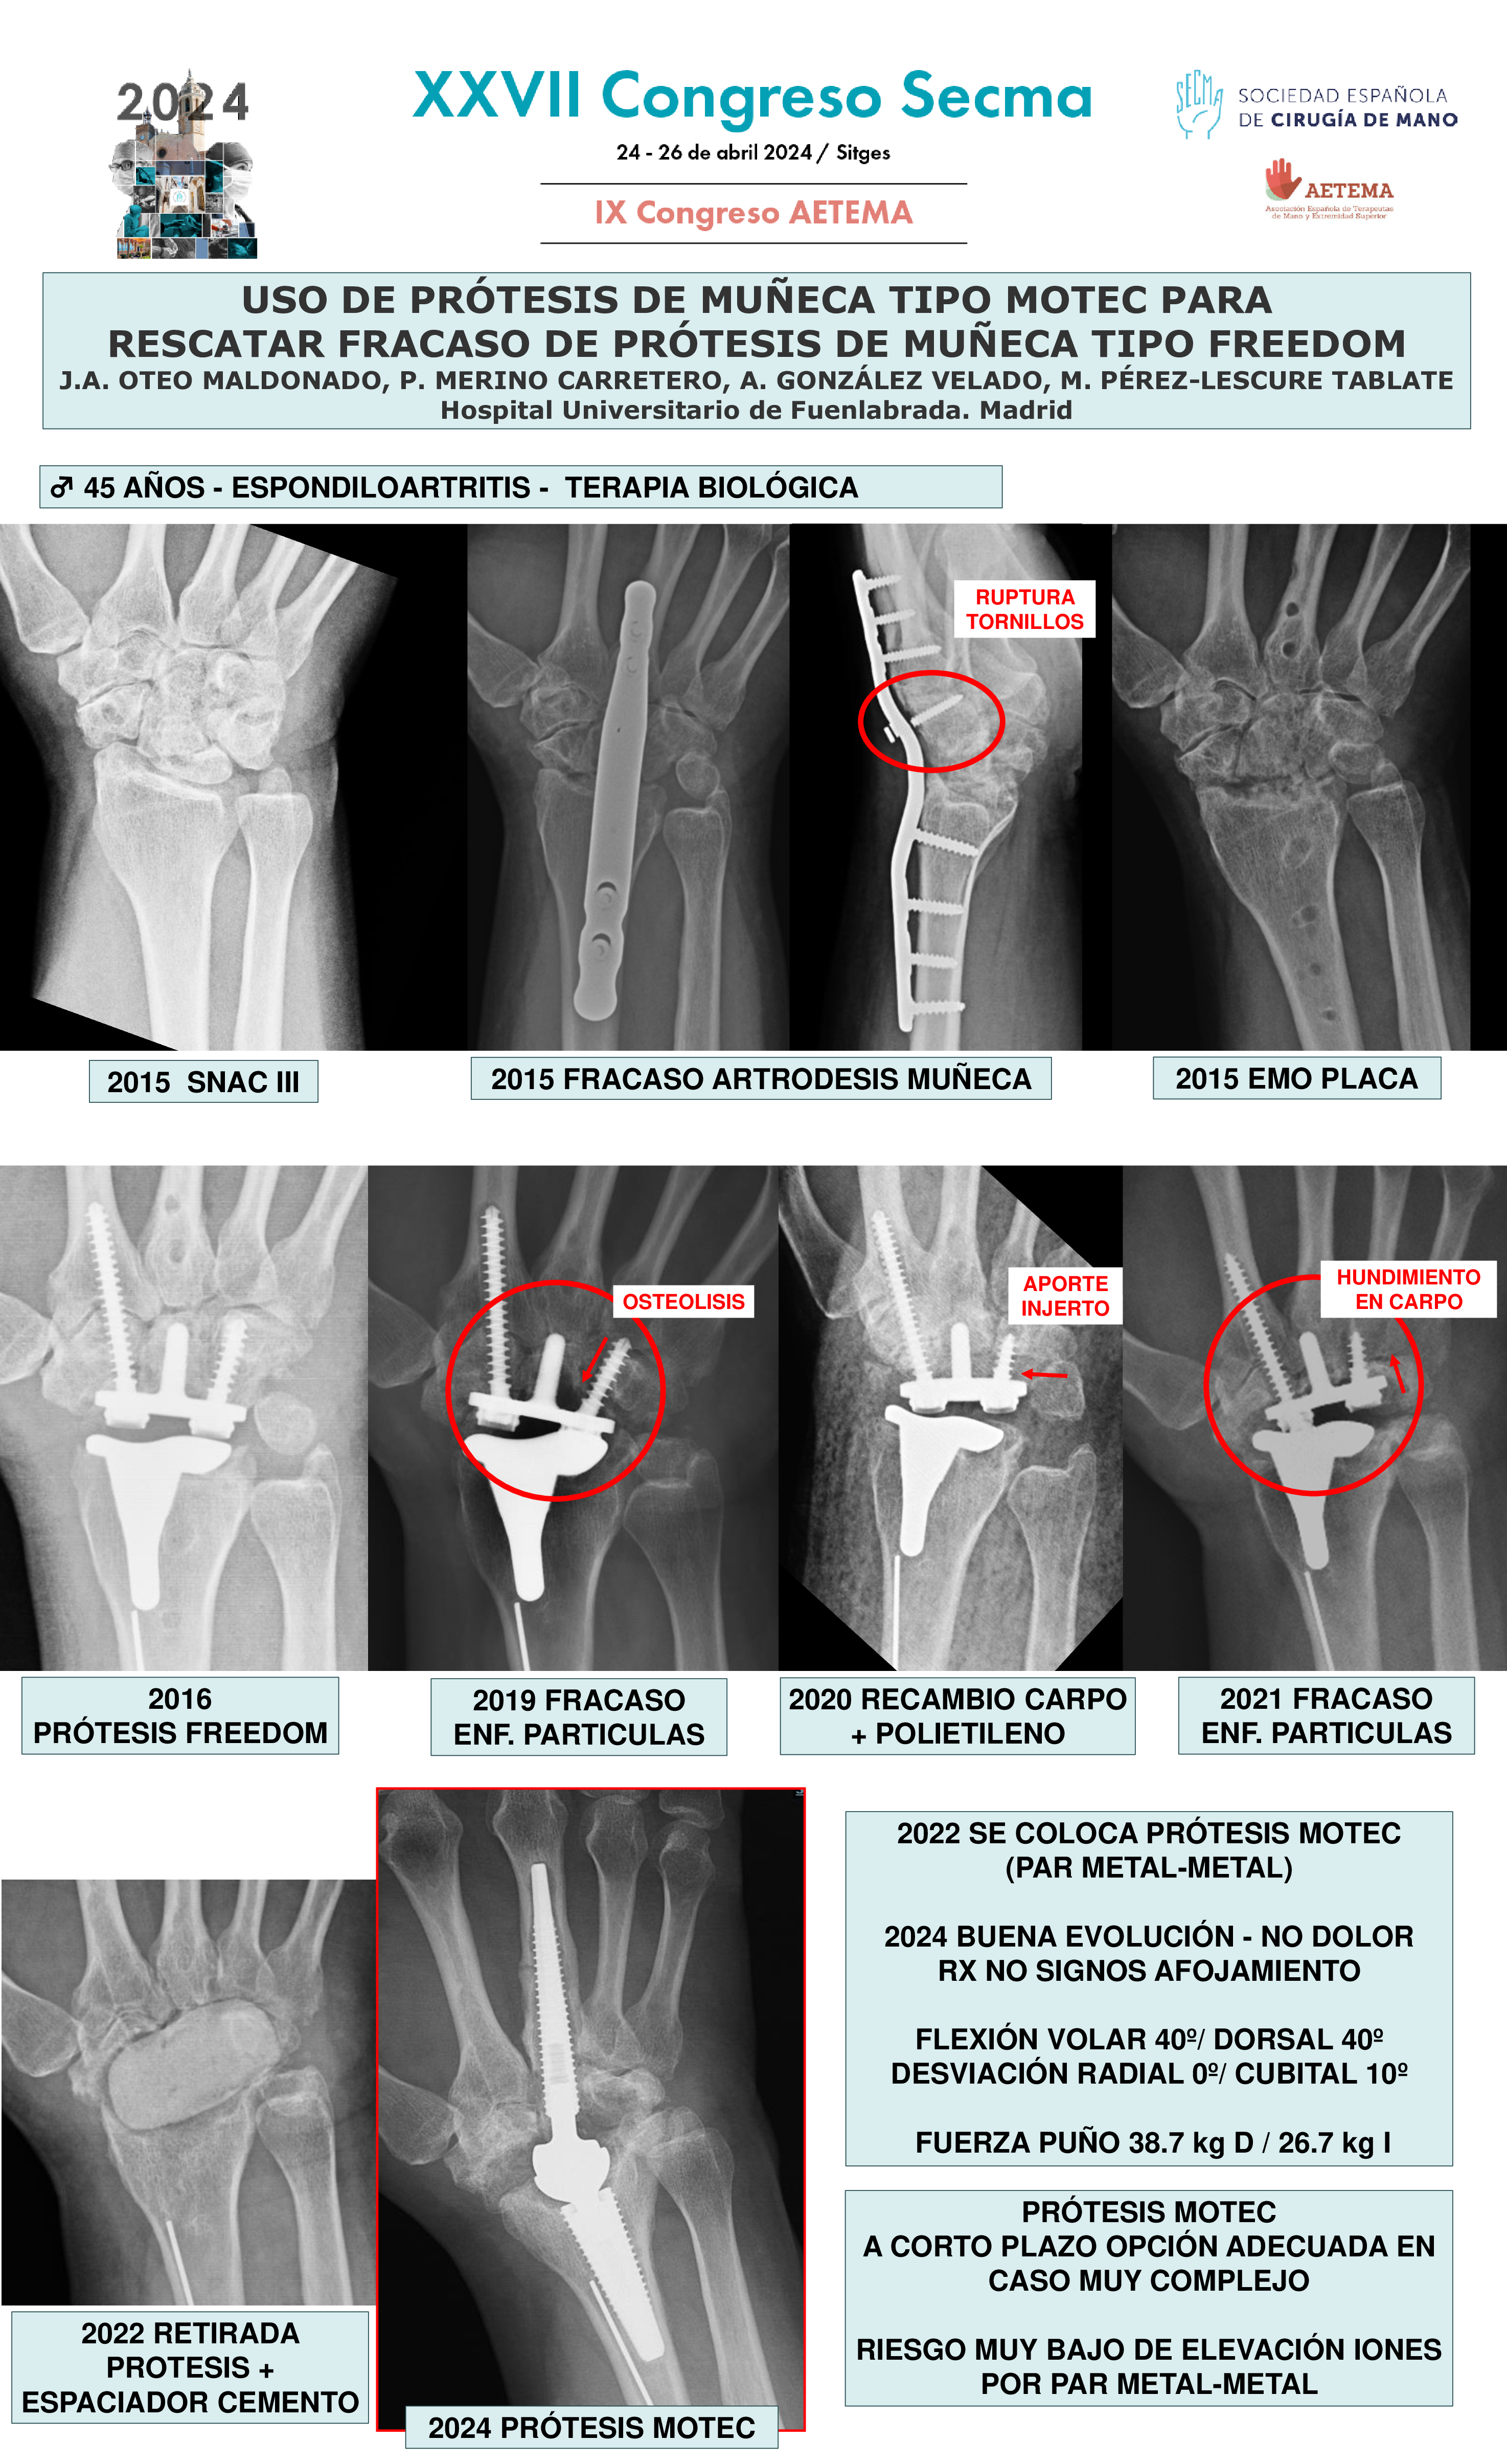

Marta Pérez-Lescure Tablate, Alberto González Velado, Patricia Merino Carretero, José Antonio Oteo Maldonado

Temática: Comunicaciones sobre Osteoartritis y enfermedades inflamatorias